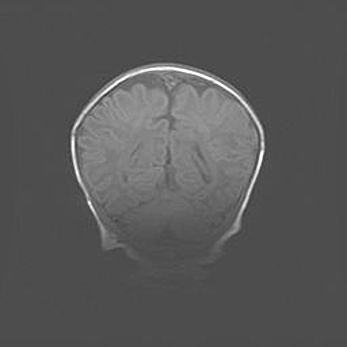

Открытая гидроцефалия.

Возраст: 9 месяцев 12 дней

Вес: 6800 г

Пол: мужской

Окружность головы: 41,5 см

Срок гестации: 28 недель

Гидроцефалия головного мозга у новорожденных имеет характерный признак: опережающий рост окружности головы приводит к визуально хорошо определяемой гидроцефальной форме сильно увеличенного в объёме черепа. Детские неврологи определяют следующие симптомы гидроцефалии у грудничков: выбухающий напряжённый родничок, частое запрокидывание головы, смещение глазных яблок к низу.